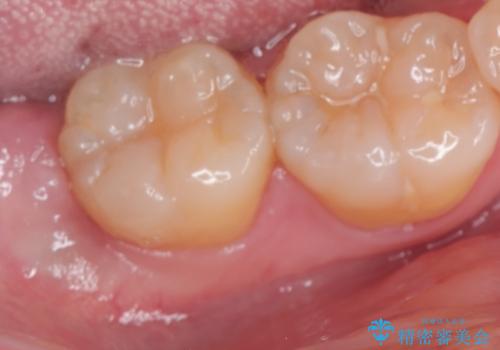

親知らず抜歯

- 20代女性

- 1ヶ月

- 2-5回

- 親知らずを抜きたいとのことで来院。CTで神経の位置などを確認し、抜歯を行いました。1週間後には抜糸に来院予定です。

しっかり麻酔が効いていることを確認し抜歯を行いました。

親知らずがあると清掃性が悪くなるため手前の歯の虫歯のリスクが上がるので抜歯をおすすめします。